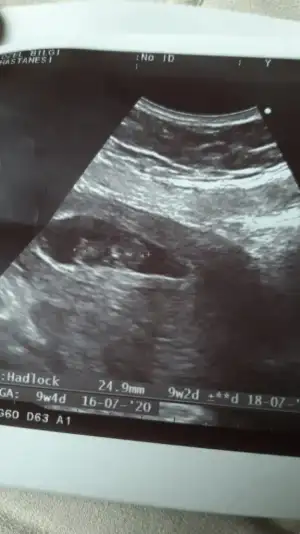

Biri 9+5 biri de 11+5. Yan donmus gibi belli oluyor mu bilemedimTekrar atsana foto

Kız gibiBiri 9+5 biri de 11+5. Yan donmus gibi belli oluyor mu bilemedim![]()

Kız gibi gibi sanki eminde değilim başka usg varmıArkadaşlar 13 haftalık yorumlarınızı bekliyorum çatladımmmmm![]()